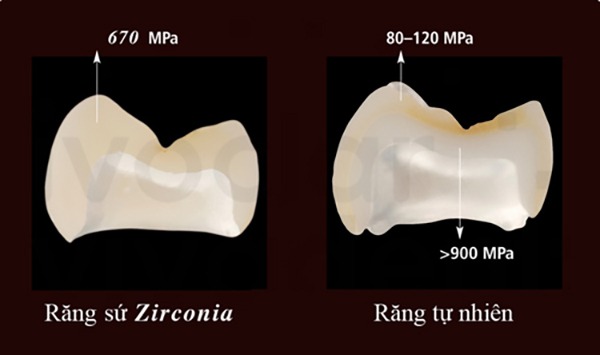

Độ cứng của răng sứ Zirconia so với răng thật